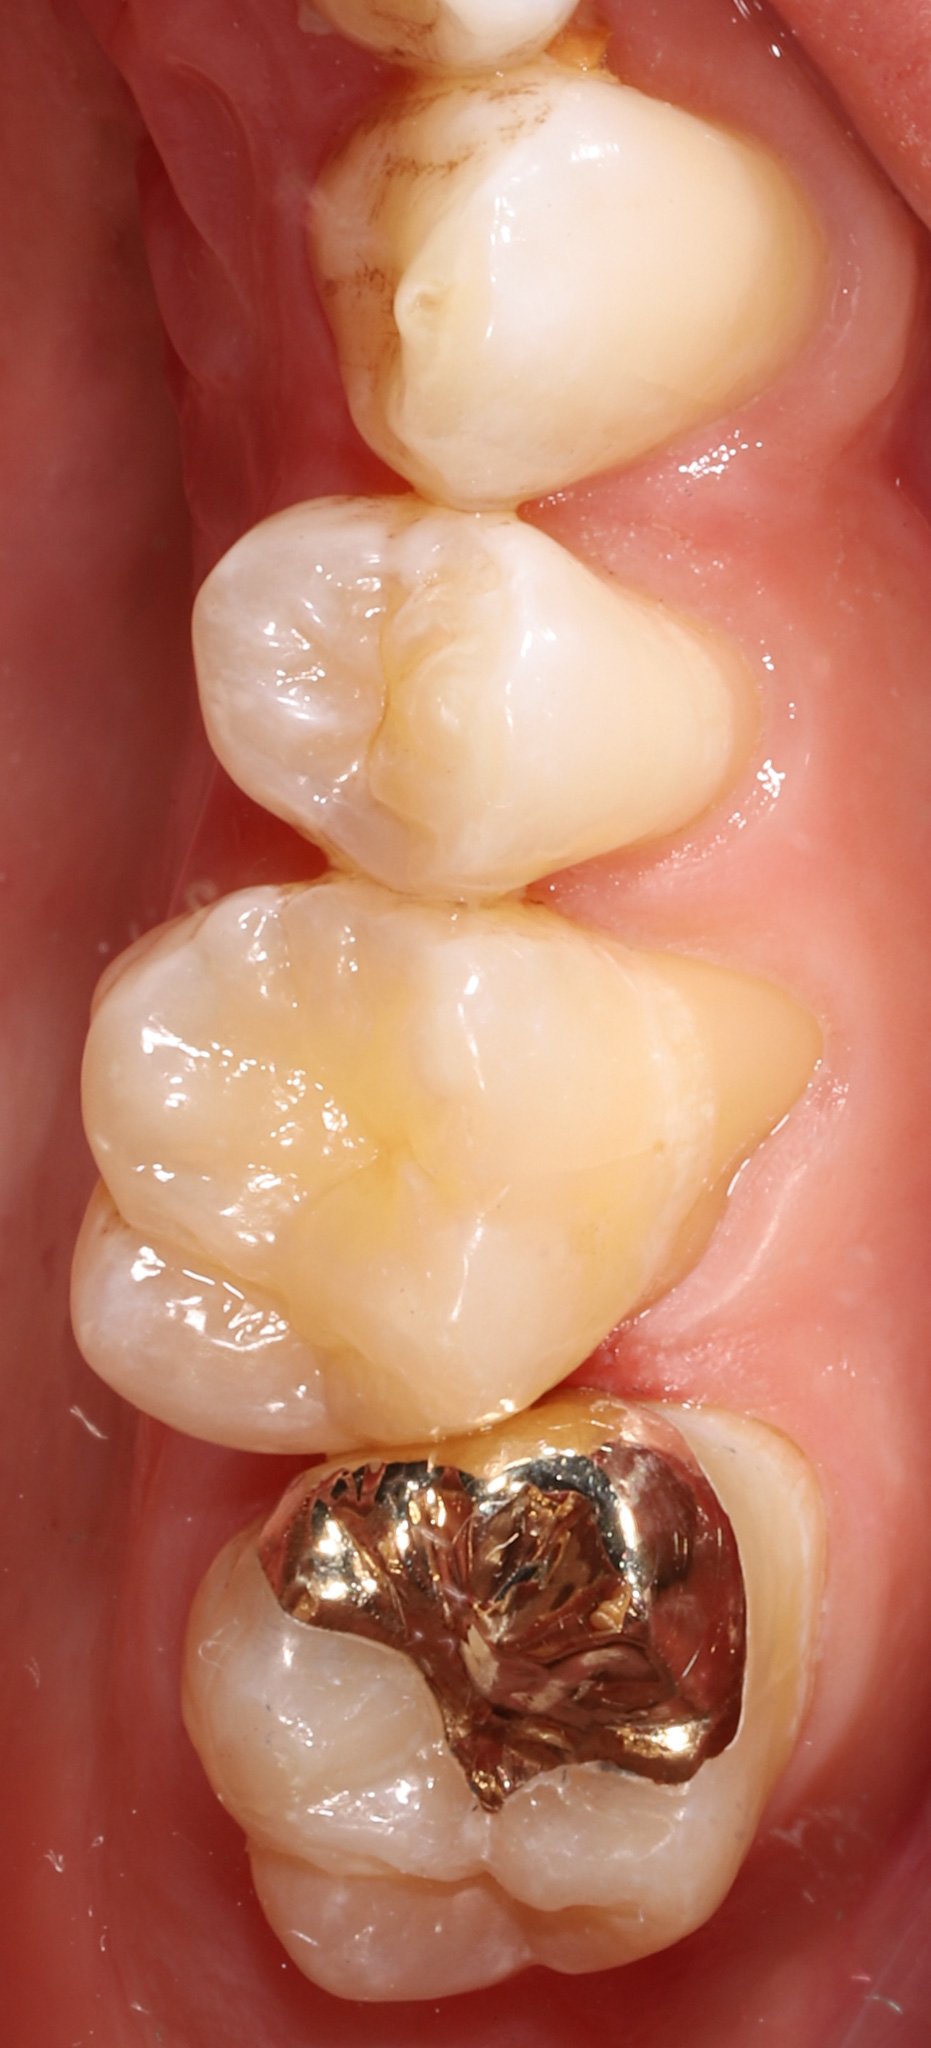

Close-up of the lower molars in a person's mouth, showing a gold dental filling on the bottom molar and the other teeth are natural and clean.

Gold Restoration

Close-up of lower molars with gold dental crowns and fillings.

Combination of gold inlay, onlay and a bonded porcelain restoration